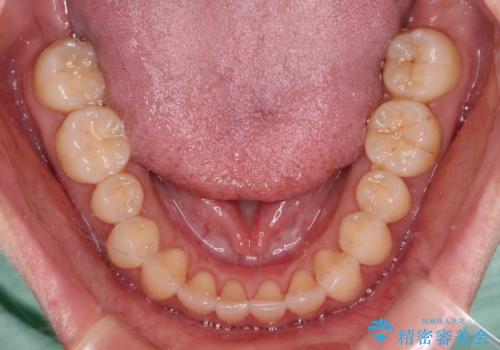

装着時間を守ってくださったので、予定通りの期間で終えることができました。インビザライン特有の、奥歯の咬み合わせの問題もなく、しっかりと歯列を改善することができました。